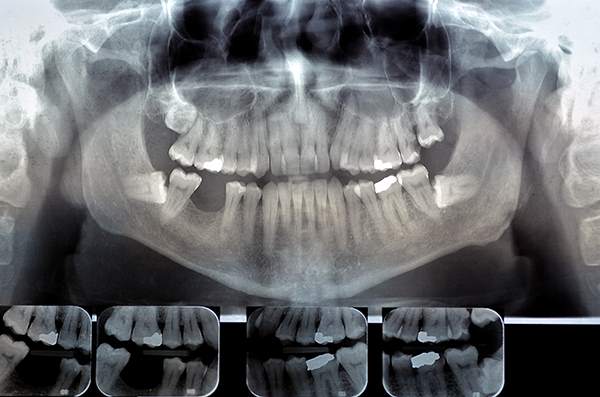

L’Ortopanoramica

Chiamata comunemente “panoramica”, questa lastra oltre ad essere fondamentale prima di un trattamento odontoiatrico, è molto utile per tracciare un bilancio dello stato della bocca in quanto permette di esaminare le zone nascoste che altrimenti non riusciremmo a vedere. Spazi interdentali, tasche gengivali, spessore osseo, parti del cavo orale che non si vedono ad occhio nudo possono infatti nascondere eventuali danni microscopici prima che possano diventare problemi difficilmente risolvibili, come granulomi e cisti.